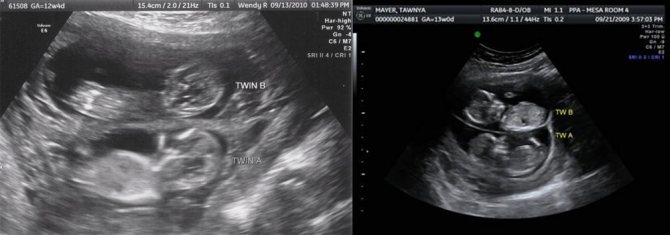

Какие параметры исследуются на ранних сроках, что видно на фото УЗИ?

Как выглядит двойня на ранних сроках? Поначалу врач видит только два темных пятнышка. Кроме того, отчетливо прослушивается биение двух сердец, видны две плаценты и два амниотических пузыря. На фото можно увидеть снимок УЗИ близнецов.

Ультразвук

Наиболее надежный метод выявления многоплодной беременности – ультразвуковое обследование. Но его проведение на ранних сроках может показать только одного ребенка. В первом триместе вероятность выявления развития многоплодности достигает 29%, во втором и третьем -96%. Иногда происходят невероятные случаи обнаружения при родоразрешении третьего ребенка, не зафиксированного при скринингах.

Когда УЗИ может не показать двойню?

В редких случаях ультразвук может не определить многоплодную беременность, даже если все внешние признаки на это указывают. По каким причинам УЗИ выдает ошибочный результат?

Чаще всего такое бывает, если будущая мамочка пропускает первое плановое УЗИ, в том числе из-за боязни, что сканирование навредит здоровью малыша. Иногда виновником становится старый аппарат УЗИ, например, в провинциальных поликлиниках или сельских больницах. В старом оборудование длина ультразвукового луча всего 18 см, из-за этого полость матки просвечивается не целиком. Картинка на мониторе выходит неполная, и второго малыша врач просто не видит.

Если будущая мама ждет троих или даже четверых малышей, бывает так, что двойню врач распознает еще на первом ультразвуке 5-6-й недель, а следующего ребенка – только на плановом сканировании.